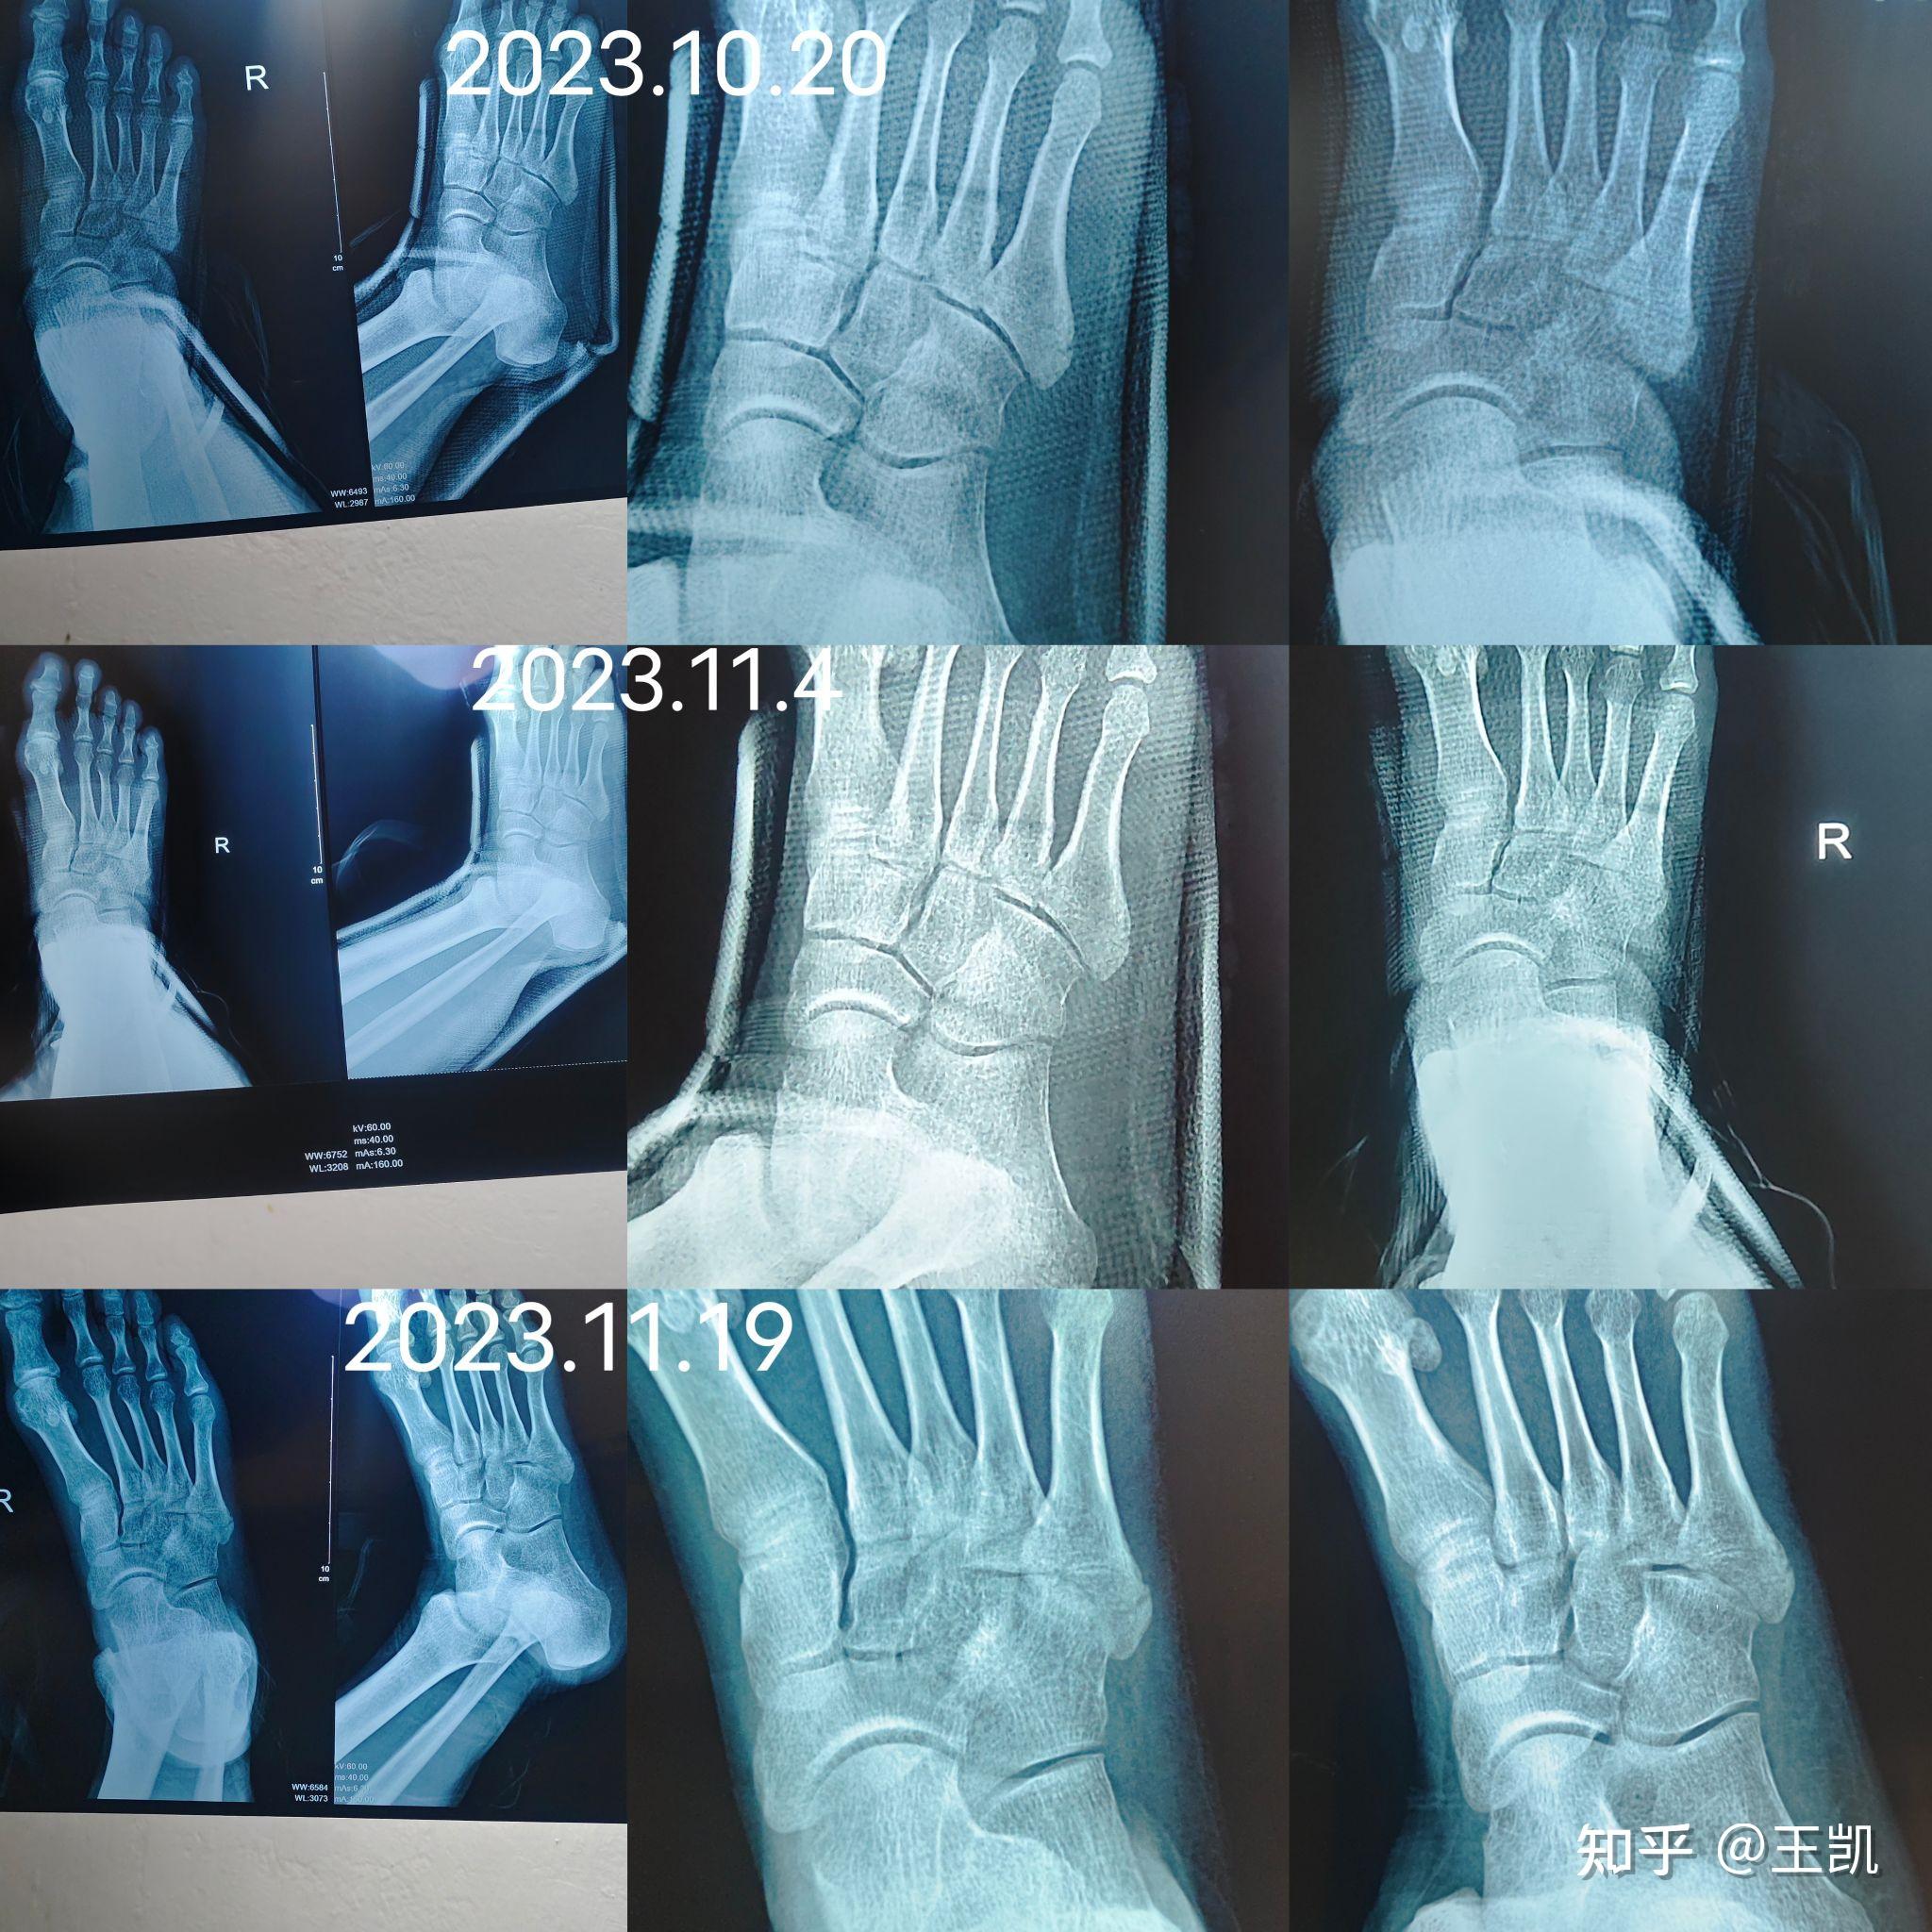

从提供的右脚照片来看,初步判断可能存在第一近节趾骨骨折的情况,但具体还需结合个人症状和进一步医学检查来确定疑似骨折观察结果片子上似乎显示第一近节趾骨有骨折的迹象,但由于照片清晰度有限,这一判断并不十分确定进一步确认建议前往医院进行X光或CT等影像学检查,以更准确地判断是否存在骨折。

病情分析跖骨骨折,一般是由扭伤车压伤重物打击足部造成的,少数是由于长途行走引起的跖骨颈疲劳性骨折基底部骨折最多,干部次之,颈部最少以横形有些多,斜形有些少受伤以后肿胀,疼疼,皮下出血,影响走路,拍x片子确诊跖骨骨折复位以后用中药接骨药外敷治疗,治疗以后适当固定就可以不。

如骨折未愈合前负重,骨折再移位局部会肿胀疼痛加重,皮肤颜色正常,皮肤温度稍高,有明显压疼X线片显示较原骨折间隙宽治疗石膏托固定制动,待骨折愈合即可可配合口服接骨续筋药物不可滥用抗生素。